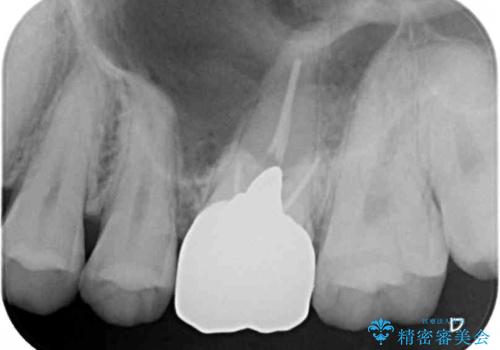

右下の銀の詰め物は、外してむし歯を除去した後、セラミックインレーにて修復することとしました。

左上の銀歯は、銀歯の下に金属の土台が入っているため、その土台を除去し、ファイバーコアにやり替えて、オールセラミッククラウンにて補綴することとしました。

適合の良いセラミック治療は、むし歯再発のリスクが低いです。